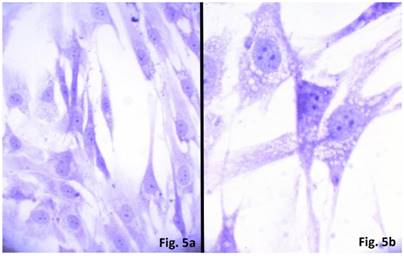

Figure 5

Cultured cells from idiopathic scoliosis concave side (the top of the deformation) stained according to Nissl. (a) x 200, (b) x 400.

The cells isolated from the concave side growth plates of the deformity (scoliosis apex) were represented by several types (Figures 4a and 4b). The first type cells were large multipolar cells with one long axon and numerous branching short processes (Figure 5a). At the center of these cells, the spherical nucleus with 1-2 nucleoli was located. Granular network (Nissl substance) was detected in the cytoplasm of the cells including processes. We found the same cells with a large oval nucleus located centrally and a narrow rim of Nissl-positive cytoplasm, turning into long processes on both ends of the cell. We have recognized uni-, bi- and pseudounipolar cells, which had Nissl substance in their cytoplasm and processes (Figure 5b). Immunohistochemical staining of the cells revealed expression of high molecular weight neurofilament NF-200 and neural βIII-tubulin as well as NF1 gene (Figures 6 a, b, c). The second type cells were large cells with round nuclei and numerous branched cytoplasmic processes. These cells expressed astrocyte protein S-100 (Figure 7a). We observed cells with clear boundaries, round or oval shape with a few processes. At the center, the cell had a large round nucleus bordered with bright rim of cytoplasm. These cells including their processes were positively stained by Cajal (Fig. 8). These cells expressed glial acidic protein GFAP, as shown in Figure 7b. We also detected the third type cells, which matched cells derived from the convex side of the deformation (data not shown).

The cultured cells, isolated from the concave side growth plates of idiopathic scoliotic deformity, were identified as neuro- and glioblasts. Morphologically neuroblasts represented multi-, uni-, and psevdounipolar cells forming multiple contacts with both the processes and cell bodies. The Nissl substance was identified and neurospecific proteins NF-200, βIII-tubulin as well as NF1 gene were expressed in the cells. Electron microscopy data also revealed some properties attributable to neural cells, namely an extended network of neurofilaments, mature and developing sinuses with vesicle and specific elongated mitochondria. The processes and the cell bodies had numerous axon hillocks ("spines") containing vesicles. Multiple contacts were revealed between the processes and the cells. The cells of the second type were round-shaped and contained a large number of processes that formed numerous contacts. Glial proteins are expressed in the processes and cells positively stained by Ramon-Kahal. According to morphological and ultrastructural data, this type of cells was referred to glioblasts.